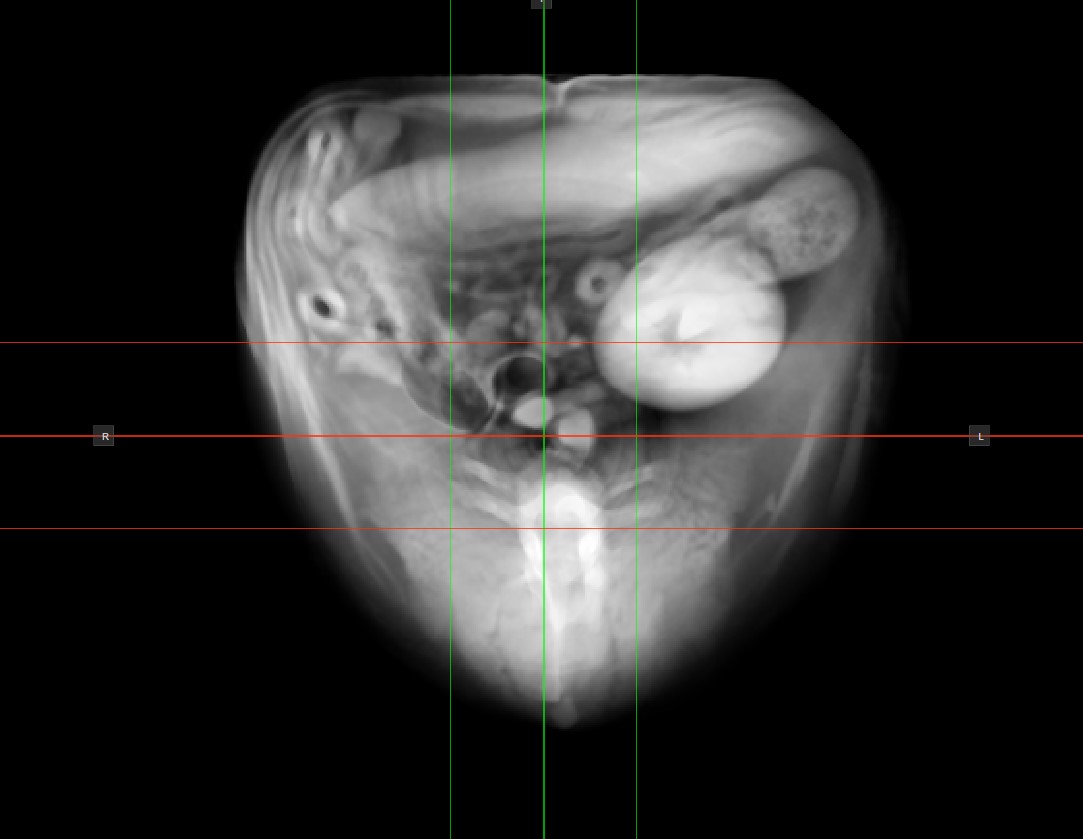

Modify Thick Slab Mode¶

The active thick slab mode in the CT Viewer can be modified by choosing an option from the Thick Slab

dropdown located in the bottom panel of the viewer.

Modify the slice thickness by dragging the Value

slider in the desired direction, or enter a specific value in the input field. The slicers will correspond to the chosen value and they will spread out to indicate the current thickness.